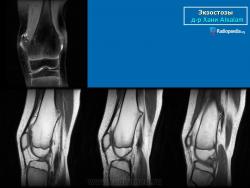

Локализация остеохондромы: частота поражения отдельных костей различна; нижний коней бедренной кости, верхние отделы плечевой и большеберцовой костей поражаются более чем у половины больных. На всем протяжении остеохондрома покрыта надкостницей. Она может быть обнаружена и в других костях, за исключением костей лицевого черепа. Все же поражение костей позвоночника, кистей рук и стоп встречается редко. При рентгенологическом исследовании видна типичная картина узкого или широкого выроста вблизи эпифизарной части пораженной кости. Обычно плотность узла неоднородная, имеются многочисленные плотные участки, соответствующие обызвествленным хрящевым долькам. Хрящевая «шапочка» большей частью не определяется, поскольку хрящ остается необызвествленным. Она может быть выявлена только при магнитно-резонансной томографии.